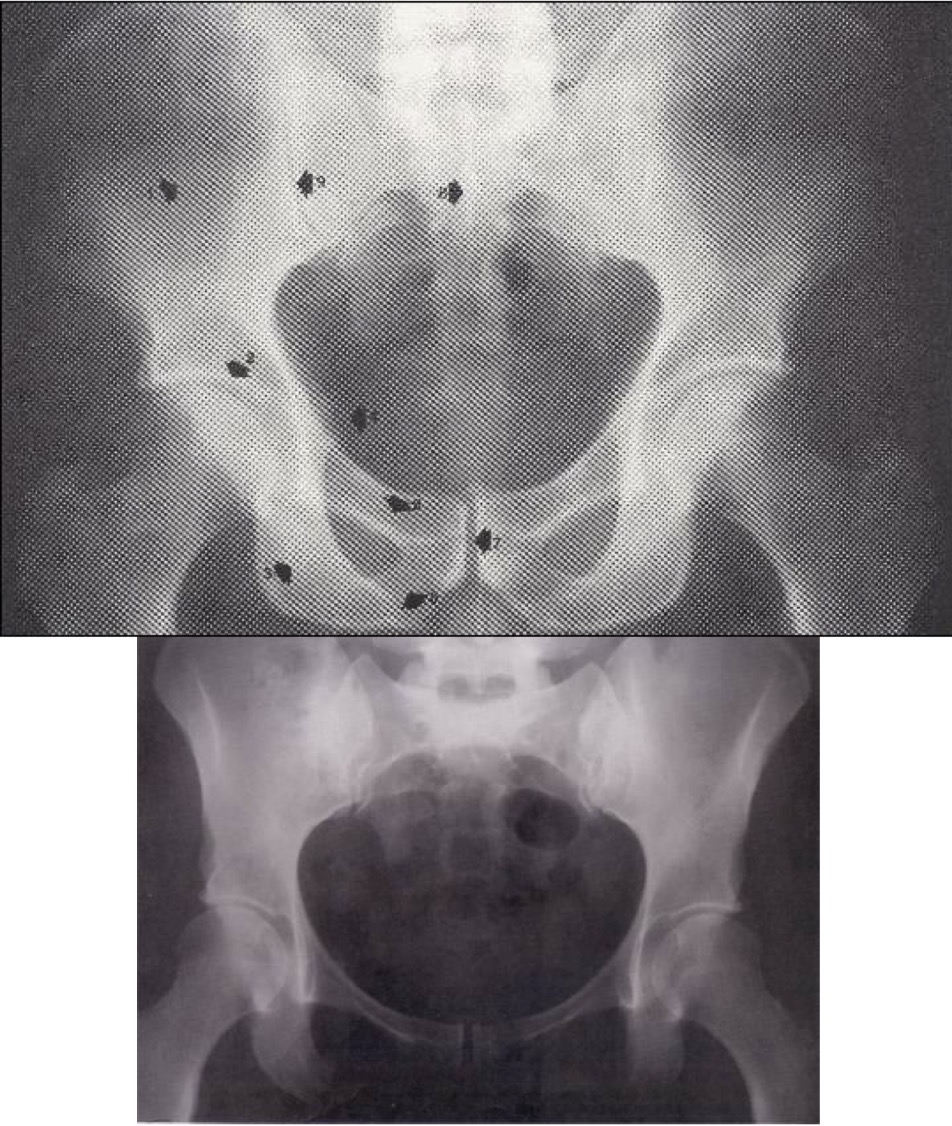

Tyrimas atliktas pacientui gulint. Matomos dubens kaulinės struktūros, juosmeninė stuburo dalis, kryžmeniniai klubų ir klubų sąnariai.

Palyginimas

Vyro dubuo yra aukštesnis ir siauresnis, angulus infrapubicus mažesnis, foramen obturatorium vertikalesnė, viršutinė dubens atvara siauresnė.